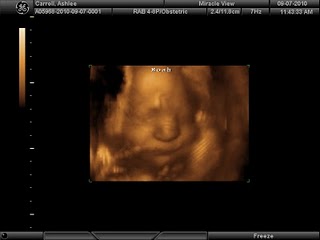

Ashlee had her three D ultrasound yesterday and baby Noah is doing well....He kept his hands and feet up at his face the whole time so it was really hard to get a good photo.....but here are a few!!!

I am sooooo excited to have you here for 6 mths and then even more excited to take trips back home to see you guys. You picked my 2 favorite picks to put on your blog, then again there were only a few that turnd out :(